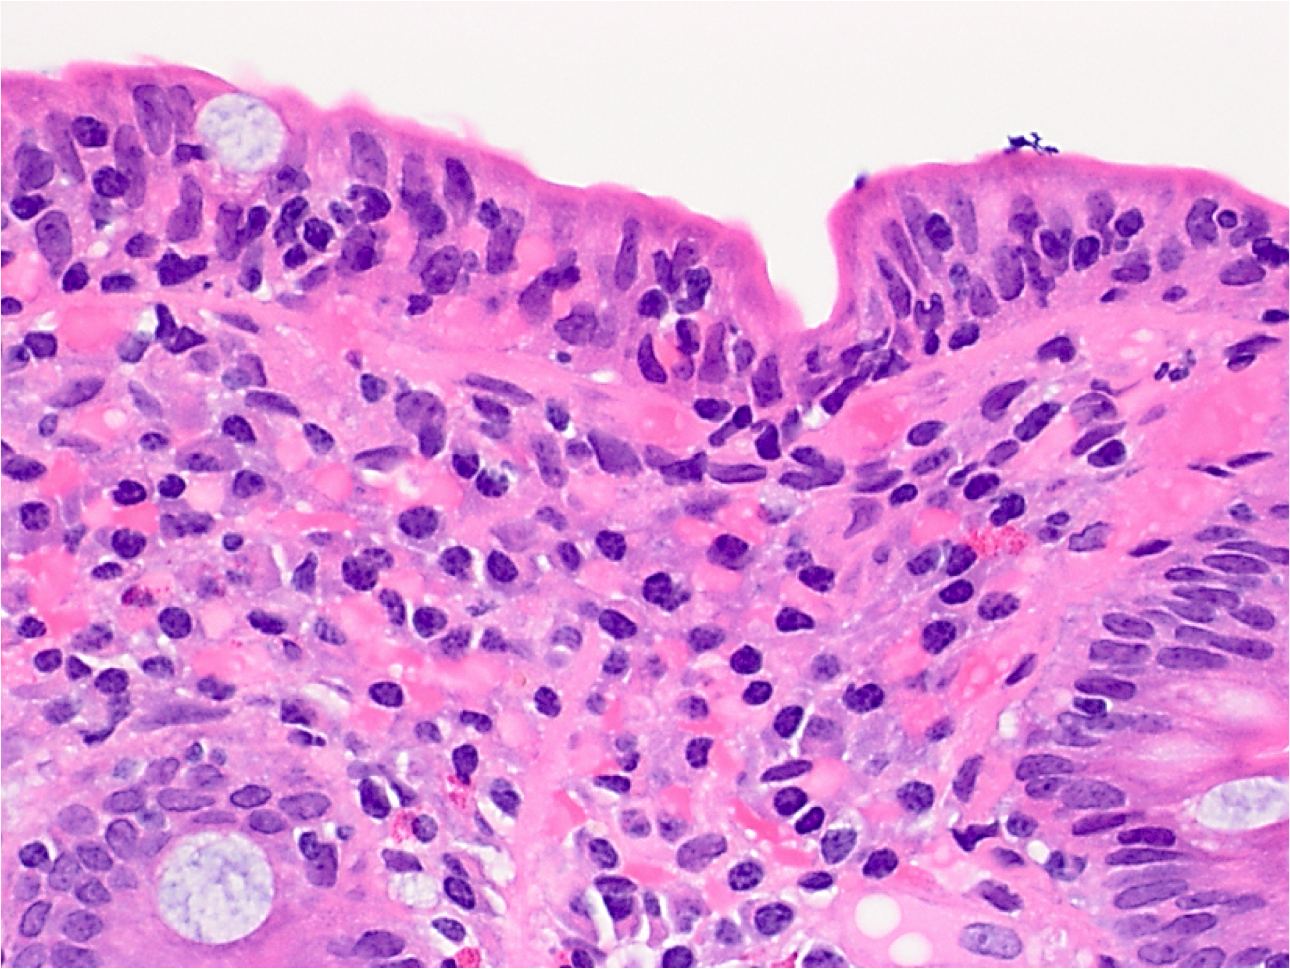

What’s this?

Celiac Disease

Increased intraepithelial lymphocytes (more than 20 per 100 epithelial cells, usually no need to count) in the superficial epithelium partially overlapping with the nuclei of the epithelial cells. Lymphocytic nuclei have dark-blue chromatin and are more round.